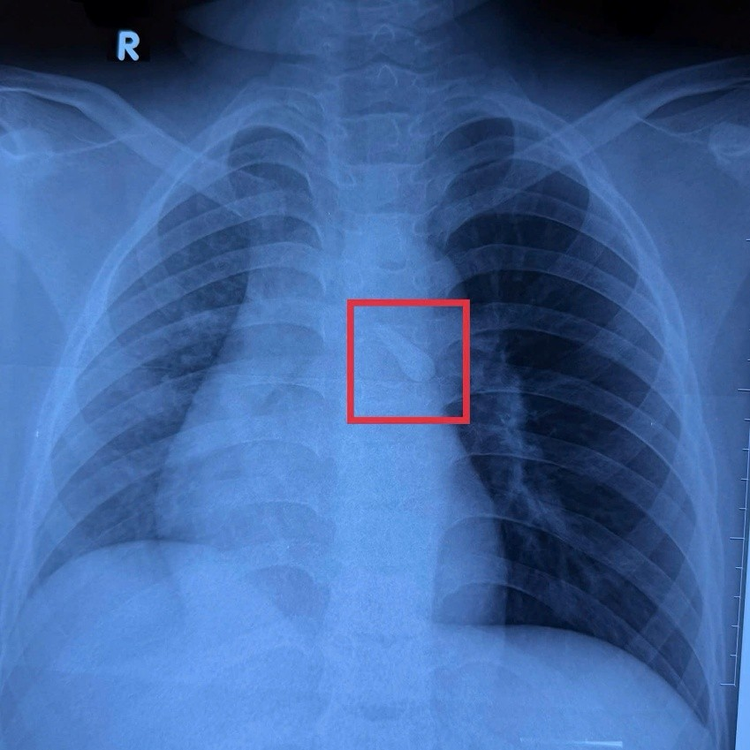

Hình ảnh X-quang của bé ghi nhận một dị vật cản quang ở khí quản. Khai thác bệnh sử và tổn thương vùng hàm mặt thấy bé bị mất răng số 21, từ đó nghĩ đến khả năng răng bị hít sặc vào đường thở sau chấn thương mà bé không để ý.

Hình ảnh X-quang của bé ghi nhận một dị vật cản quang ở khí quản - Ảnh BVCC